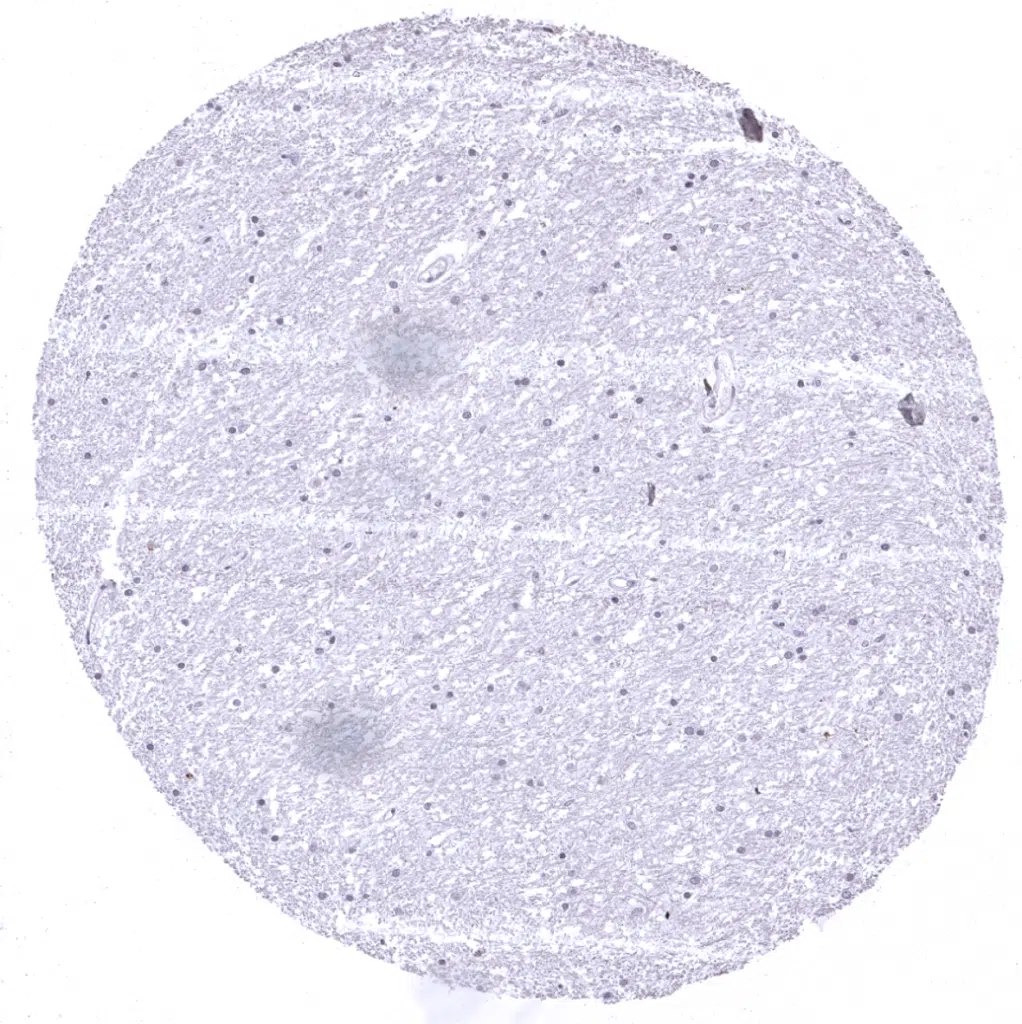

Cerebrum, grey matter